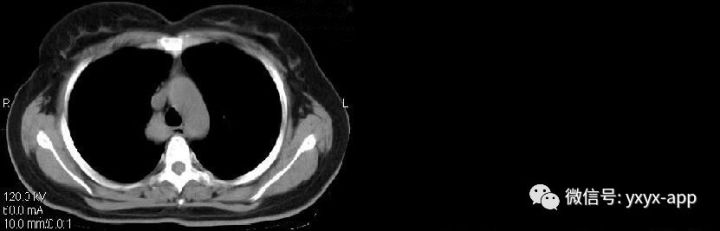

CT值在50-60hu之间

肚肚丫头:右上后纵隔、气管右旁、脊柱前方可见类圆形软组织密度影,与气管及食管均关系,增强后无明显强化,考虑囊肿,起源待定。

CT表现:纵隔旁支气管囊肿其典型形态为圆形、类圆形、水滴形、长条形,偶为分叶状,边缘均清楚锐利,内部密度多较均匀。肺内型表现为单发的气囊肿、液囊肿、液-气囊肿或多发囊肿,边界清楚,囊壁薄而均匀,可合并肺发育不良、肺隔离症、肺气肿及胸廓塌陷等其他肺内畸形。CT值差异较大,多为20~30HU,最高可达80HU,反映囊肿内容物的不同成分,囊肿不与支气管相通时形成含液囊肿,与支气管相通时囊液会全部或部分排出,形成含气囊肿或含气液囊肿。如有感染、出血或囊壁受到刺激可以使壁增厚、毛糙,囊液也可以变得更粘稠,或者分泌的黏液含有高蛋白成分、钙乳样物质等,均可导致囊肿内密度增高,从而CT表现为软组织密度、实性肿块。CT增强扫描有助于判断囊壁及囊腔内容物的强化程度,提示诊断。支气管囊肿的强化特征为囊内容物无强化,囊壁可强化,是由于囊壁含有平滑肌成分,如合并感染、肉芽组织增生,囊壁可增厚、强化。